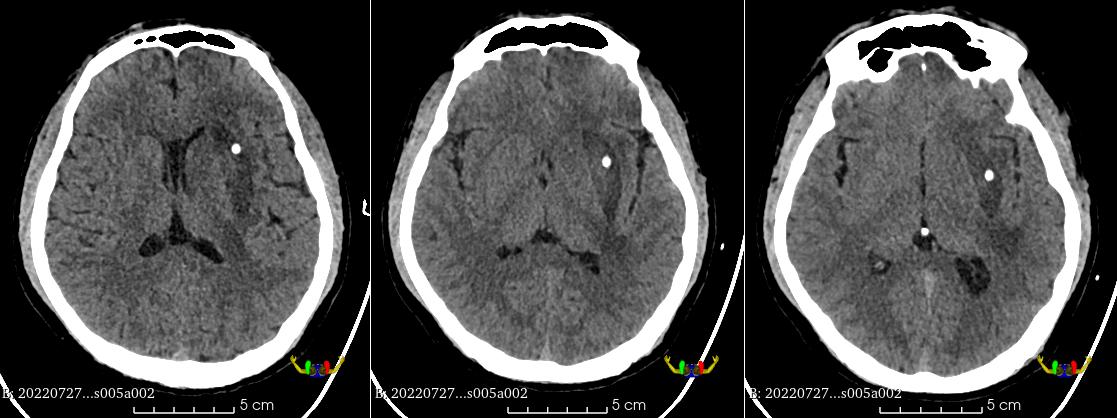

术前CT示血肿分层